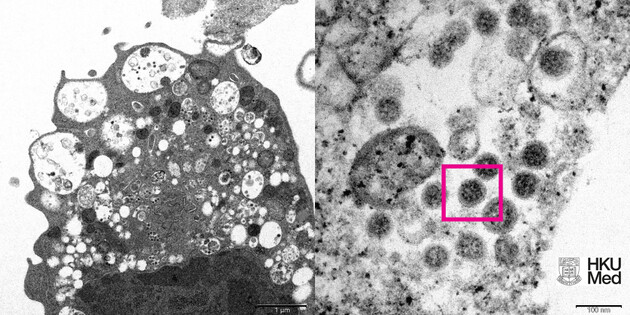

В Польше обнаружили первый случай нового штамма коронавируса "Омикрон". Его зафиксировали в Катовице, информирует RMF24.

Ученые отмечают, что "Омикрон" распространяется гораздо быстрее других штаммов.